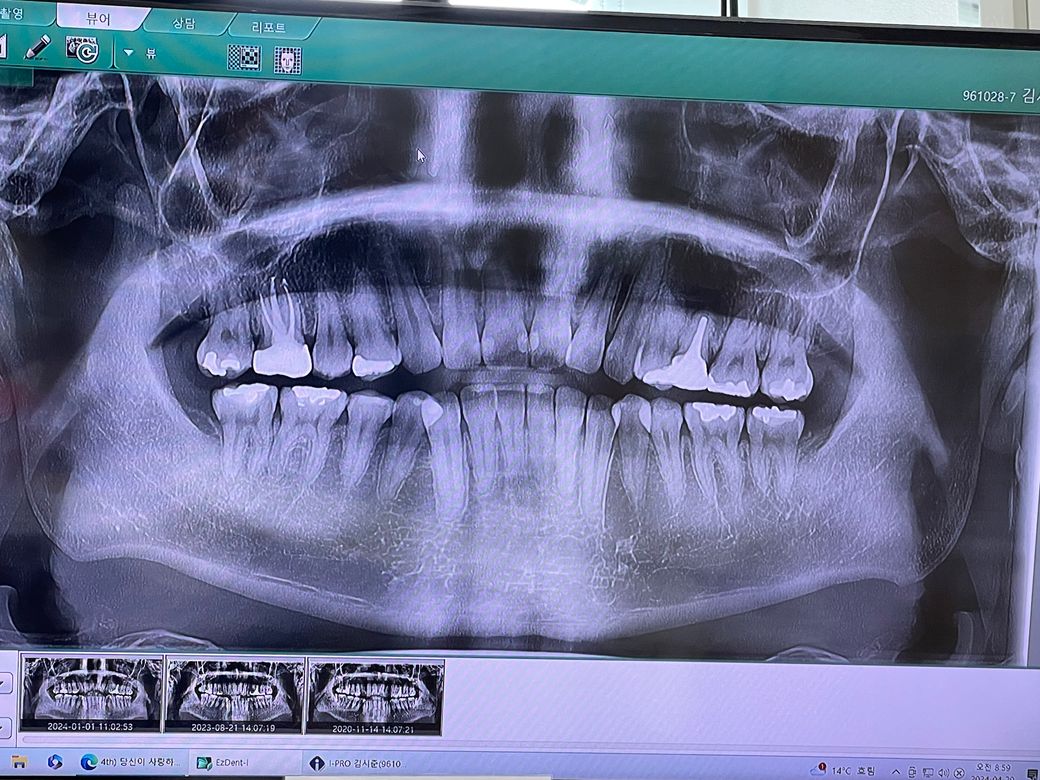

옛날에 치아에 포스트를 세우고 크라운을 씌운 치아가 크라운 씌운지 오래돼서 교체를 하였습니다 지르코니아로 포스트 기둥은 그대로 두고 크라운만 교체를 하였는데 크라운 교체할 때 망치 같은 걸로 뽑고 교체 르루 했는데 그 이후부터 잇몸이랑 주변 부위에 통증이 너무 심합니다 그래서 치과를 방문하니 치아 뿌리 쪽에 염증이 생겼다고 했는데 교체하기가 충격으로 인해 생긴 건가요? 그래서 어떻게 해야 하나 여쭤보니 여기서 손을 더 대면 임플란트를 할 수 있으니 그대로 두 자고 하시더라고요 근데 제가 치아 뿌리 염증에 대해서 찾아보니 치근 단 절제술도 있고 잇몸을 열어서 염증을 긁어내는 치료방법도 있던데 왜 안 해주시고 그냥 쓰라고 하시는 건지 궁급합니다 그리고 무조건 임플란트밖에 방법이 없다고 하셔서 정말 그런 건가요 그대로 두고 더 써보자고 하시는데 점점 염증도 커지고 나중에는 더 심해져서 위에 치근단 치료 같은 것도 못 받는 게 아닌지 궁급합니다 통증도 점점 심해지고 주변 치아까지 망가지는 게 아닌지 걱정됩니다 어떤 치료를 받아야 할까요 사진 첨부합니다

• 2번 째 사진

포스트 치료가 돼 있는 경우에는 근관 치료가 어려운 경우가 많습니다. 재신경 치료가 가능하다면 재신경 치료를 받는 것이 좋으며 제 신경 치료를 받기 힘들거나 치아뿌리에 금이 갔을 경우에는 발치를 해야 할 경우도 생기게 됩니다. 자세한 확인을 위해 치과에서 진료를 받아보는 것을 권유드립니다

• 안녕하세요 치과의사 김철진입니다. 교체할때 충격으로 치아에 염증이 생기거나 그렇진 않습니다. 기존에 치료를 한부위에 염즈잉 처음부터 잇엇다면 크라운 교체 전에 미리 고지를 햇어야되지 않을까 싶습니다. 파노라마 사진보다는 작은 엑스레이 사진을 한번더 찍어보셔야될것같습니다 .